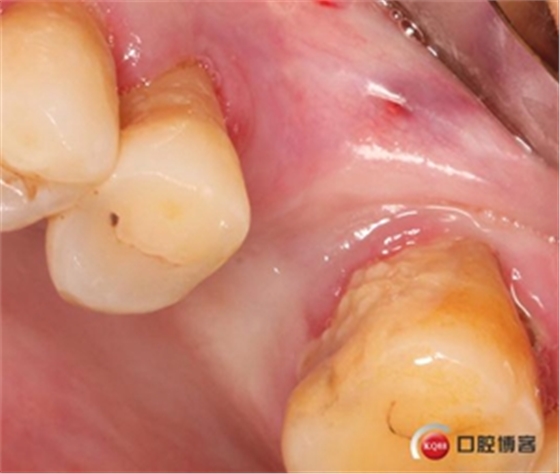

切開翻瓣。

植入一顆4.5x11.5mm長度植體。